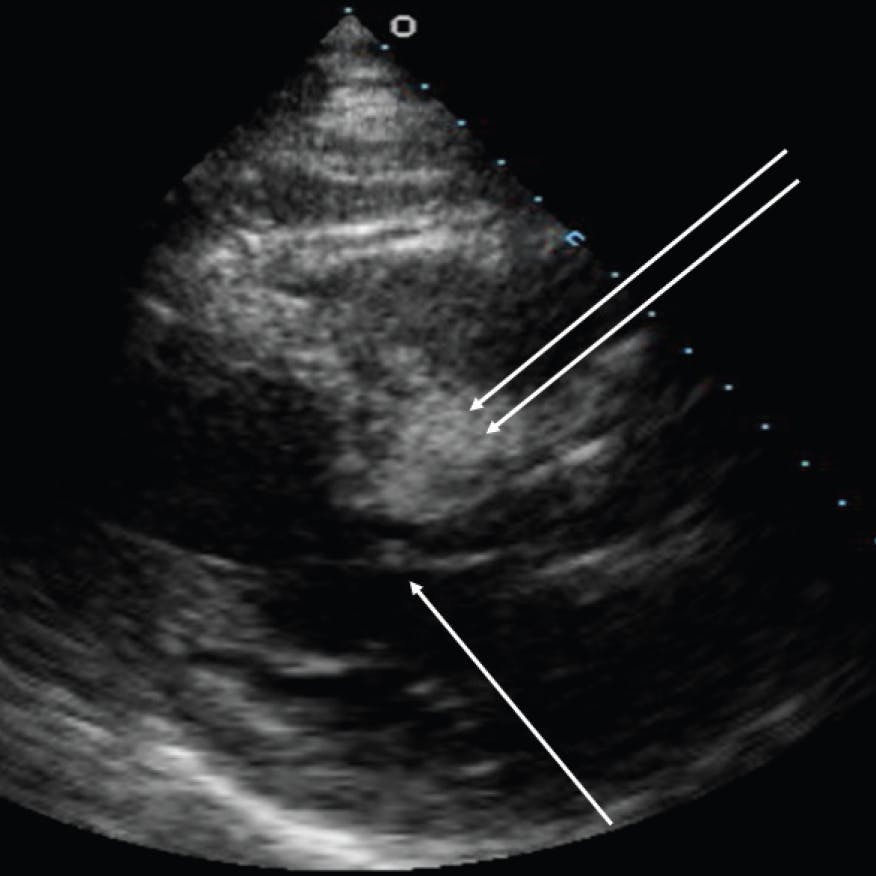

A transthoracic echocardiogram is obtained during balloon occlusion, and 0.5 to 1 mL of either angiographic contrast or echo contrast is injected while echo images are obtained. The parasternal long axis and apical two-chamber views are ideal for demonstrating the septum and the SAM contact point. Patients with ideal septal anatomy demonstrate a bright contrast effect in the proximal septum at the point of SAM contact (Figure 4). It is important to be sure that the septal perforator does not also supply other areas of myocardium, such as the inferior wall not targeted for ablation. If the anatomy is appropriate to continue, it is confirmed that balloon remains occlusive by injecting contrast into the left coronary artery before proceeding with alcohol injection.

Figure 4. Parasternal long-axis view showing the SAM contact point on the septum (single arrow), and the contrast effect during injection into the first septal perforator (double arrow) demonstrating that the targeted septal artery will deliver the alcohol to the desired location in the septum.